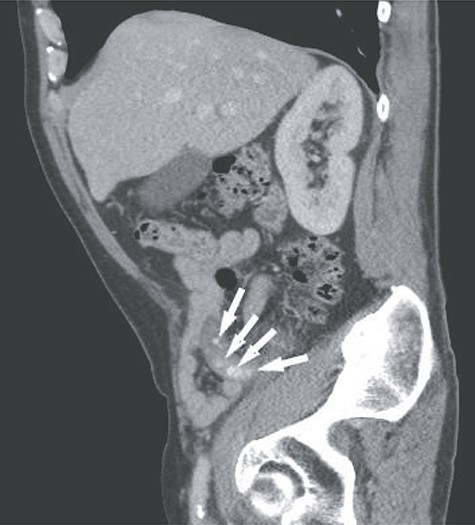

A 66-year-old male patient who had undergone bilateral blepharoplasty 3 days earlier was referred to our acute care surgical service with a 24-hour history of increasing right lower quadrant pain accompanied by nausea, vomiting and anorexia. Clinically he was found to be afebrile with a soft abdomen and focal tenderness at McBurney’s point. Significant laboratory investigations revealed a leukocytosis of 13.0. A CT scan of the abdomen confirmed the diagnosis of appendicitis with an impacted appendicolith at the appendicular outlet and a number of additional appendicoliths distributed along the length of the appendicular lumen (Figs 1–2). The patient was surgically consented for a laparoscopic appendicectomy with intraoperative video recording. At laparoscopy an inflamed and focally necrotic appendix was located coiled over the cecum (Figs 3–4). The appendectomy was completed without complication, and the specimen longitudinally transected in the operating room prior to pathological submission. This revealed four appendicoliths within the lumen, all measuring over 5 mm at their smallest diameter (Fig. 5). Pathology confirmed acute suppurative appendicitis with transmural necrosis, with the appendicoliths described as faeculent in origin. The patient’s post-operative recovery was uneventful.

Sagittal view of the abdominal CT showing multiple appendicoliths within a dilated appendix (white arrows).